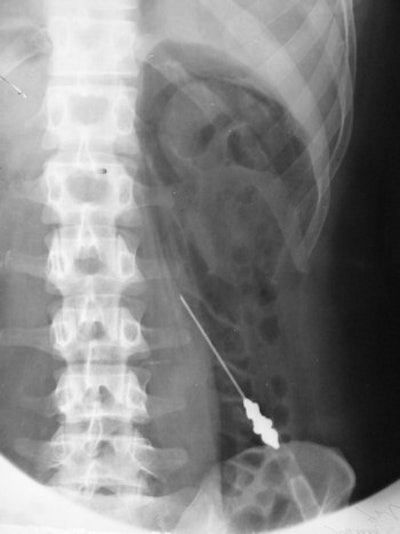

In later years, the technique was combined with tomography to show the adrenal gland. The examination illustrated below was performed in 1943.

This retroperitoneal air study was performed in 1943 using a 10-cm needle.Diagnostic pneumoperitoneum/gynecography